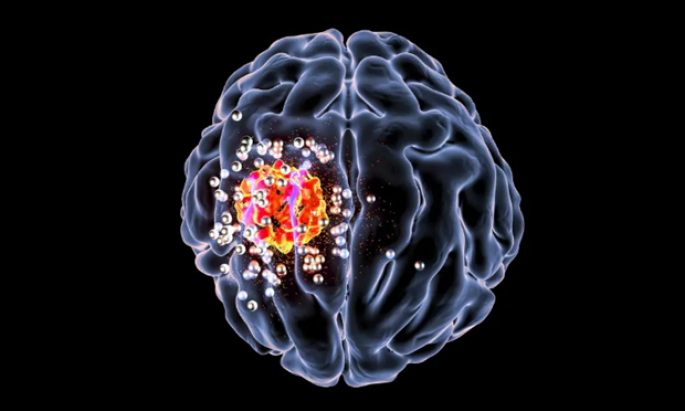

Phương pháp mới hỗ trợ điều trị ung thư não bằng liệu pháp miễn dịch

Các nhà khoa học cho biết phương pháp hydrogel mới giúp tạo miễn dịch đặc hiệu với tế bào gốc ung thư, từ đó mở ra cơ hội sống cho các bệnh nhân bị ung thư tái phát.